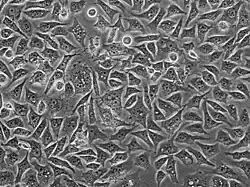

PC3 (PC-3) is a human prostate cancer cell line used in prostate cancer research and drug development.[1] PC3 cells are useful in investigating biochemical changes in advanced prostate cancer cells and in assessing their response to chemotherapeutic agents. PC3 cells are also used to study viral infection in mammalian cells that exhibit an immune response.[2]

The PC3 cell line was established in 1979 from bone metastasis of grade IV of prostate cancer in a 62-year-old Caucasian male.[3] These cells do not respond to androgens, glucocorticoids or fibroblast growth factors,[4] but results suggest that the cells are influenced by epidermal growth factors.[5] PC3 cells can be used to create subcutaneous tumor xenografts in mice to investigate the tumor environment and therapeutic drug functionality.[6]

PC3 cells have high metastatic potential compared to other pancreatic cells of DU145 cells, which have a moderate metastatic potential, and to LNCaP cells, which have low metastatic potential. Comparisons of the protein expression of PC3, LNCaP, and other cells have shown that PC3 is characteristic of small cell neuroendocrine carcinoma.[4]

PC3 cells have low testosterone-5-alpha reductase and acidic phosphatase activity, and do not express PSA (prostate-specific antigen). Furthermore, karyotypic analysis has shown that PC3 are near-triploid, having 62 chromosomes. Q-band analysis showed no Y chromosome. From a morphological point of view, electron microscopy revealed that PC3 cells show characteristics of a poorly-differentiated adenocarcinoma. They have features common to neoplastic cells of epithelial origins, such as numerous microvilli, junctional complexes, abnormal nuclei and nucleoli, abnormal mitochondria, annulate lamellae, and lipoidal bodies.